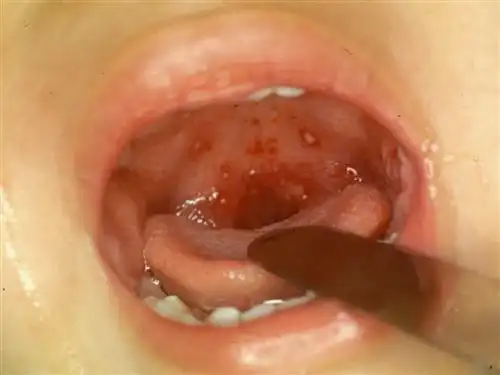

疱疹性咽峡炎是由肠道病毒感染引起的儿童急性上呼吸道感染性疾病

疱疹性咽峡炎